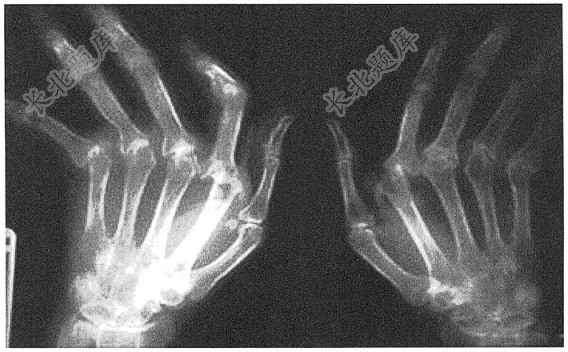

- 单项选择题患者女,56岁,反复关节疼痛10年,活动受限2年,可能的诊断是( )

A、类风湿性关节炎

B、痛风性关节炎

C、骨质疏松

D、肾性骨病

E、退行性变